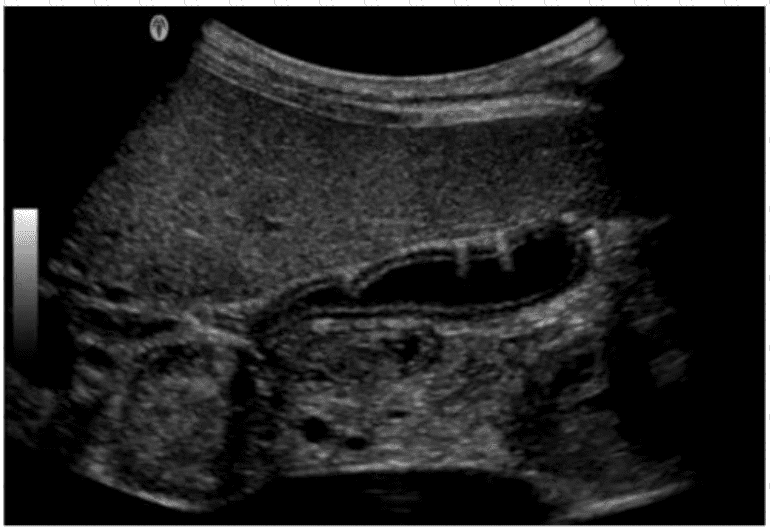

The ultrasound image shows echogenic foci with dirty shadowing and reverberation artifacts within the gallbladder wall and lumen. These features are characteristic of emphysematous cholecystitis, a severe, life-threatening variant of acute cholecystitis caused by gas-forming organisms (e.g., Clostridium or E. coli) infecting the gallbladder wall.

Sonographic features of emphysematous cholecystitis:

Echogenic gas within the gallbladder wall or lumen

Reverberation or "dirty" shadowing artifacts

May show intramural gas bubbles or "ring-down" artifact